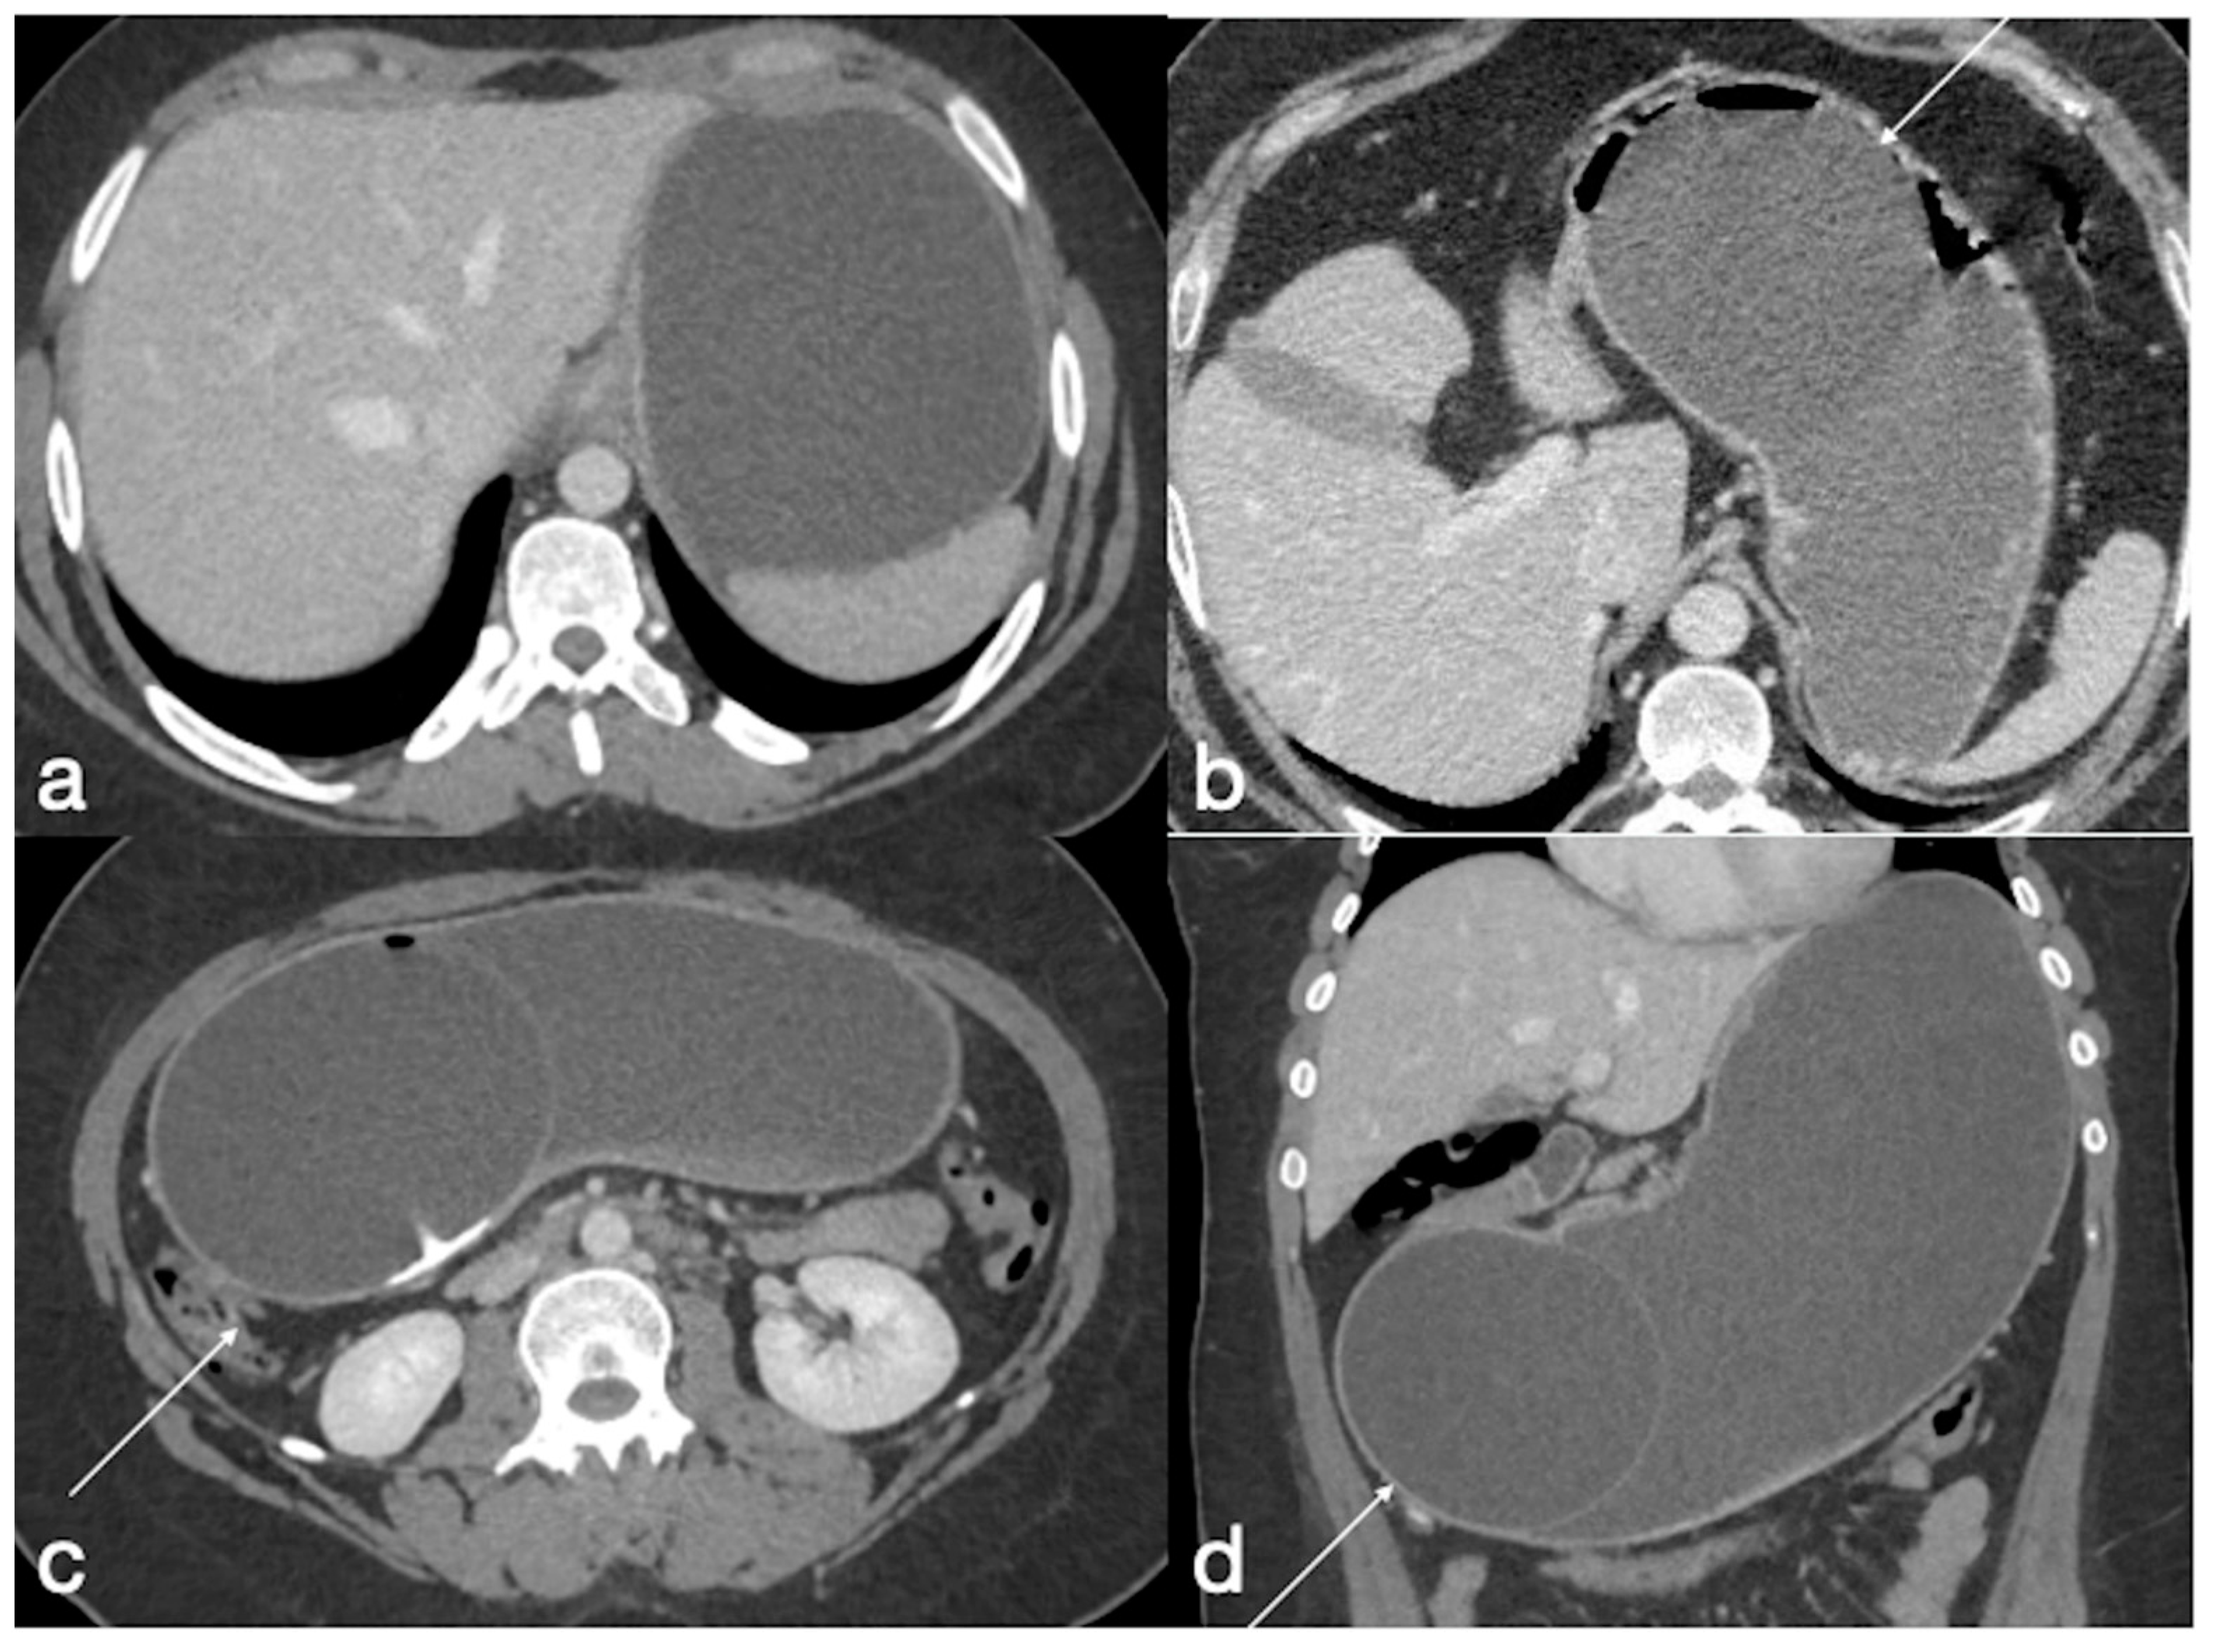

- Spleno-porto-mesenteric vein thrombosis (PVT)